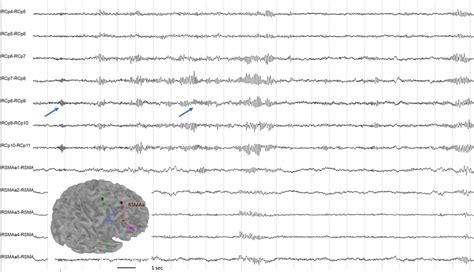

One of the primary uses of the 21-channel EEG is in the diagnosis and management of epilepsy. EEG can detect abnormal brain activity patterns, such as spikes and sharp waves, which are characteristic of epileptic seizures. It can also help classify the type of epilepsy and localize the seizure focus, which is crucial for determining the best treatment strategy. During a seizure, the EEG can show a clear pattern of abnormal electrical discharge, aiding in the diagnosis. Between seizures, the EEG may reveal interictal epileptiform discharges (IEDs), which are indicative of an increased risk of seizures. Long-term EEG monitoring, including ambulatory EEG and video-EEG, is often used to capture seizure events and correlate them with clinical symptoms. This is particularly important for patients with non-epileptic seizures or those whose seizures are difficult to control with medication.